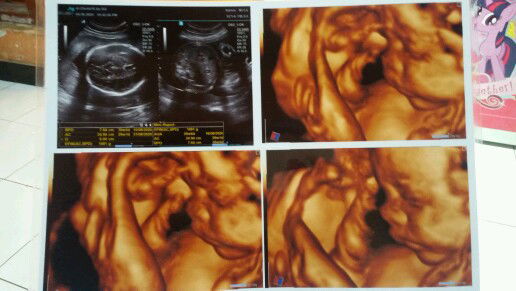

USG 4D

Alhamdulillah... sehat2 trus ya nak..?? 29W